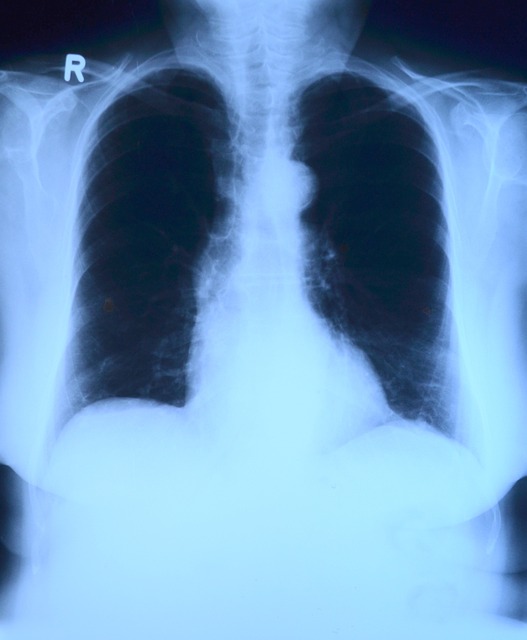

3.1. 폐결핵 검사

폐결핵 검사는 흉부 X-선 촬영을 통해 이루어지며, 폐결핵균에 의한 감염 여부를 확인합니다. 만약 이상 소견이 발견되면, 추가적인 객담 검사 등을 통해 확진 절차를 밟습니다. 결핵은 전염성이 강한 질병으로, 음식물 조리 및 제공 과정에서 타인에게 쉽게 전파될 수 있기 때문에 엄격히 관리되고 있습니다. 폐결핵 의심 소견이 없으면 보건증 발급이 가능하지만, 질환 확진 시에는 완치 이후에야 발급받을 수 있습니다.